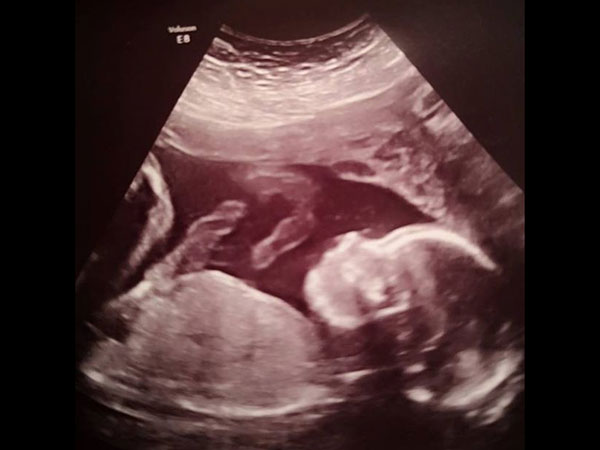

20 வாரங்களில் செய்யக் கூடிய வழக்கமான ஸகேனில் கருவில் உள்ள குழந்தையின் தலை சரியான அளவில் இல்லாமல் இருந்தது கண்டுபிடிக்கப்பட்டது. மேலும் ஸ்பைனா பிஃபிடா பாதிப்பின் காரணமாக, குழந்தை நடப்பதில் பாதிப்பு ஏற்படலாம் என்பதும் கண்டறியப்பட்டது. இதனால் மருத்துவர்கள், இந்த தம்பதிக்கு கருக்கலைப்பை பரிந்துரைத்தனர்.

கருக்கலைப்பை பெற்றோர் ஏற்றுக் கொள்ளாத நிலையில், மருத்துவர்கள் கருப்பை அறுவை சிகிச்சை என்னும் புதிய சிகிச்சையைப் பற்றி கூறினர். இந்த வகை சிகிச்சையில் குழந்தை பிறப்பதற்கு முன்னரே, குழந்தையின் பிரச்னையை சரி செய்வது என்று கூறினார். அதாவது, குழந்தையை தாயின் கருப்பையில் இருந்து வெளியில் எடுத்து, அந்த குழந்தையின் முதுகுத்தண்டு பிரச்னையை சரி செய்து, மீண்டு தாயின் கருவில் வைப்பது தான் இந்த சிகிச்சை. இந்த சிகிச்சை மூலம் குழந்தை சாராசரி வாழ்க்கையை வாழ இயலும்.